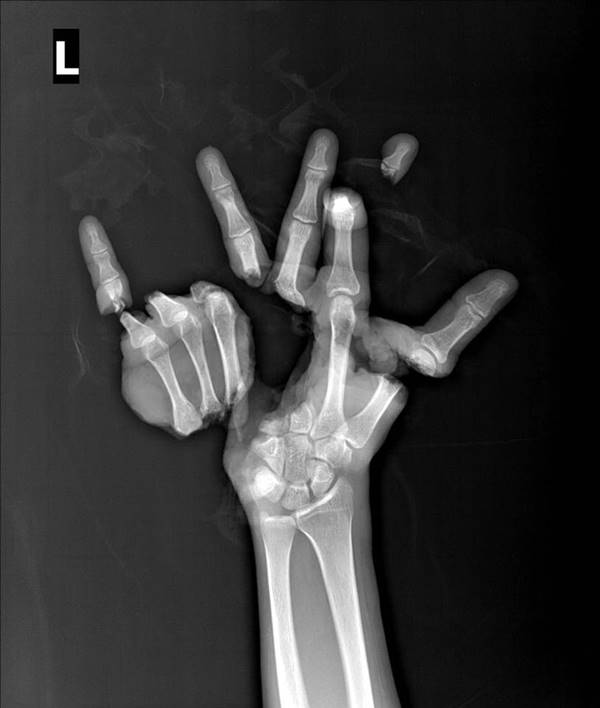

คุณหมอเล่าว่า เคสดังกล่าว ผู้ป่วยบาดเจ็บจากจากถูกเครื่องปั๊ม ตัดนิ้ว ตัดฝ่ามือขาด ออกเป็น ชิ้น ๆ นิ้วหัวแม่มือ ปลายนิ้วชี้ โคนนิ้วกลาง นางนิ้วก้อย และฝ่ามือขาดใช้เวลากว่า 10 ชั่วโมง ในการผ่าตัด กระทั่งสามารถต่อนิ้วได้เกือบหมด แต่มีนิ้วชี้ที่มีปัญหาในเรื่องการอุดตัน การที่จะแก้ใหม่นั้น จะต้องแก้ทั้งมือ และเอามือที่เหลือทั้งหมดที่ประกอบเสร็จแล้วเป็นเดิมพัน

คุณหมอเลยตัดสินใจตัดนิ้วชี้ออก เพียงหนึ่งข้อเพื่อไม่ให้มือที่เหลือตกอยู่ในความเสี่ยง

โดยพบว่าคนไข้นั้นไม่เห็นภาพก่อนที่จะเข้ารับการผ่าตัดของตนเองเนื่องจากไม่กล้าดู

ซึ่งเมื่อคนไข้ได้ดูแล้ว จากที่สอบถามว่าทำไมถึงไม่ต่อนิ้วชี้ให้

ก็ความรู้สึกเปลี่ยนไปเป็นขอบคุณที่ช่วยผ่าตัดให้มือกลับมาอยู่ในสภาพที่คล้ายเดิมที่สุดแล้ว